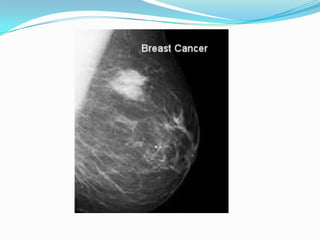

 Mammograms use x-rays to look for breast cancer.

 The mostfamiliar use of x-rays is checking for broken bones  However, x-rays are also used in other ways.  For example, chest x-rays can spot pneumonia.  Mammograms use x-rays to look for breast cancer.